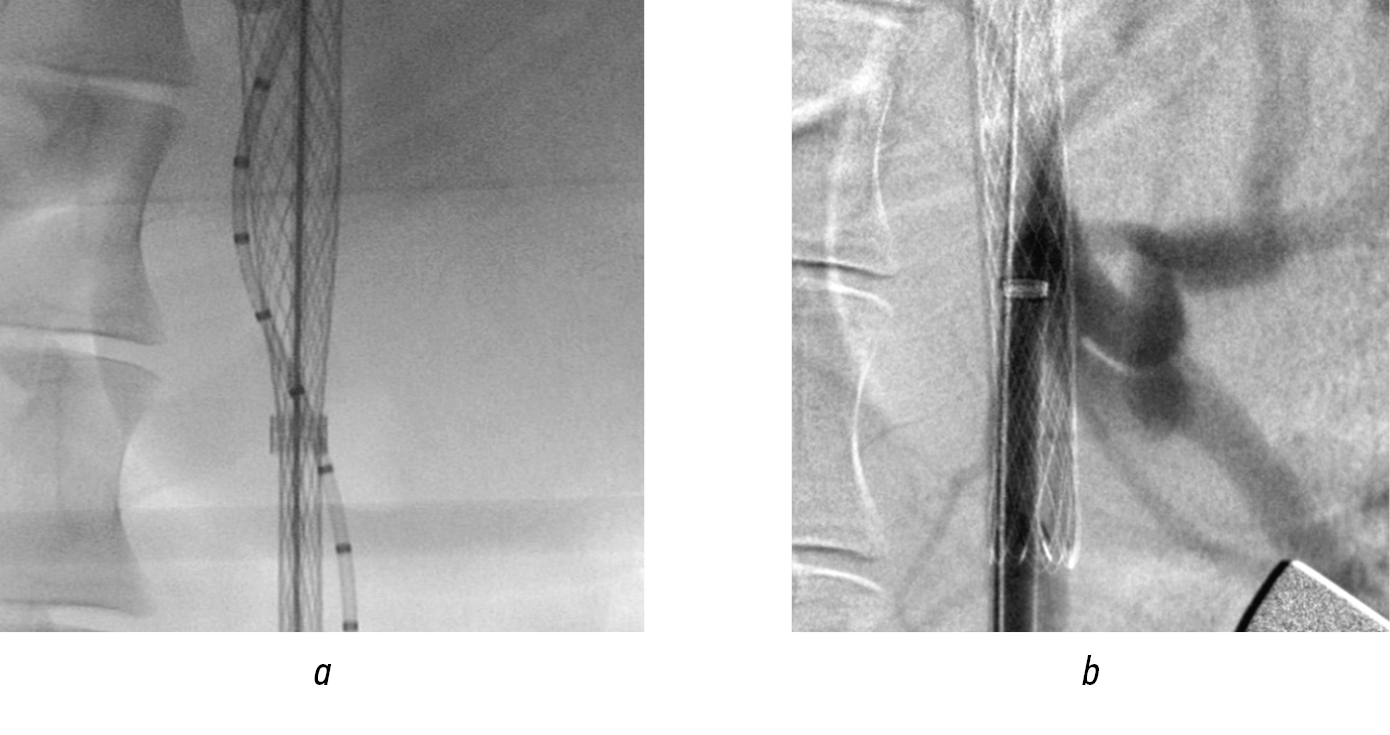

Endoprosthesis replacement of the suprarenal abdominal aorta. Under X-ray control, along a guidewire, the main trunk of a universal stent graft was implanted into the site of origin of the celiac trunk and superior mesenteric artery (Fig. 14, a). During control aortography with heparin, the orifices of the visceral branches, blocked by the installed stent, were clearly visualized (Fig. 14, b), which created the RoadMap mask.

Fig. 14. Endoprosthetics of the suprarenal aorta: а — implantation of the main trunk; b — control angiogram

Alternately, personalized fenestration of the graft wall was performed in the projection of the orifices of the celiac trunk and superior mesenteric artery. Balloon dilatation of the fenestrated openings was subsequently performed with the implantation of lead modules into the visceral branches (Figs. 15 and 16). After their installation, dilatation with a balloon catheter was mandatory. In the control image, the structure was passable, and the visceral branches were clearly contrasted without signs of residual stenosis in the fenestrated area (Fig. 17).

Fig. 15. Branching of the ventral trunk mouth: а — personalized fenestration over the ventral trunk mouth; b — balloon dilatation of fenestration; c — implantation of visceral branching

Fig. 16. Stages of endoprosthetics in the suprarenal aorta (continued): а — personalized fenestration over the mouth of the superior mesenteric artery; b — balloon dilation of the fenestration opening; c — implantation of the module into the superior mesenteric artery

Fig. 17. Angiograms after prosthetics of visceral branches: a — control after implantation; b — post-dilation of modules; c — control snapshot